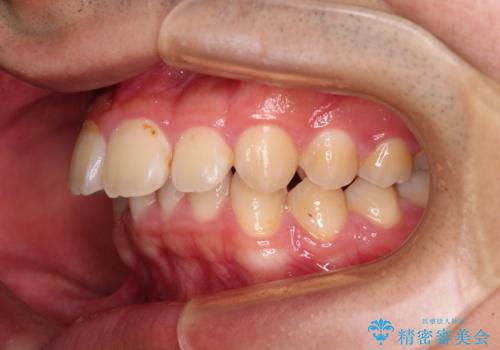

- 深く咬みこんだ前歯と、それに伴い前方に突出した上顎前歯を気にして来院された患者様です。

下顎の歯列は、奥歯が前方に傾斜し、前歯が上顎の歯の付け根に食い込むように内側に傾斜していました。

また、左右の犬歯の位置関係は上顎歯列が前方に位置する咬み合わせとなっており、インビザライン単体で治療するよりは、ワイヤー装置や補助装置を併用した方がより良い仕上がりになることが期待されました。

来院時は学生であったので、補助装置により上顎臼歯を後方に移動させ、下顎歯列はワイヤー装置による傾斜を改善させ、就職のタイミングでインビザラインにて仕上げていくこととしました。